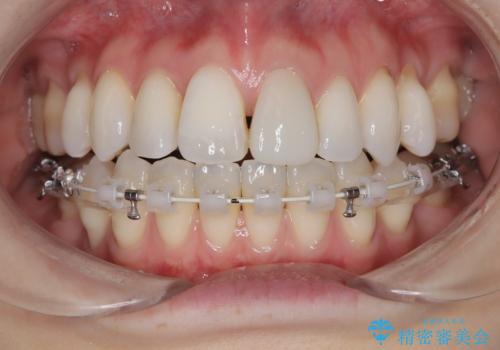

ハーフリンガル矯正|上下4本の抜歯で叢生を改善し、美しい歯並びへ

- 患者様は、歯並びの乱れ(叢生)を整えたいが、前歯の突出感は気にならないとのことで来院されました。診察の結果、全体的な歯列のスペース不足により抜歯が必要と判断。しかし、前歯を大きく下げる必要はなかったため、小臼歯の中でも5番(第二小臼歯)を抜歯する治療計画を立てました。装置は、上顎が舌側(リンガル)、下顎が表側(審美ワイヤー)のハーフリンガル矯正を採用し、目立ちにくさと効率的な歯の移動を両立しました。

抜歯によって歯を並べるためのスペースを確保。その後、ハーフリンガル矯正を用いて、上顎は舌側から、下顎は目立ちにくいワイヤーで歯を誘導し、歯列全体を整えました。治療期間を通じて、噛み合わせのバランスも改善し、機能的にも審美的にも理想的な仕上がりとなりました。患者様からは「目立たずに矯正でき、きれいな歯並びになって嬉しい」とご満足いただきました。